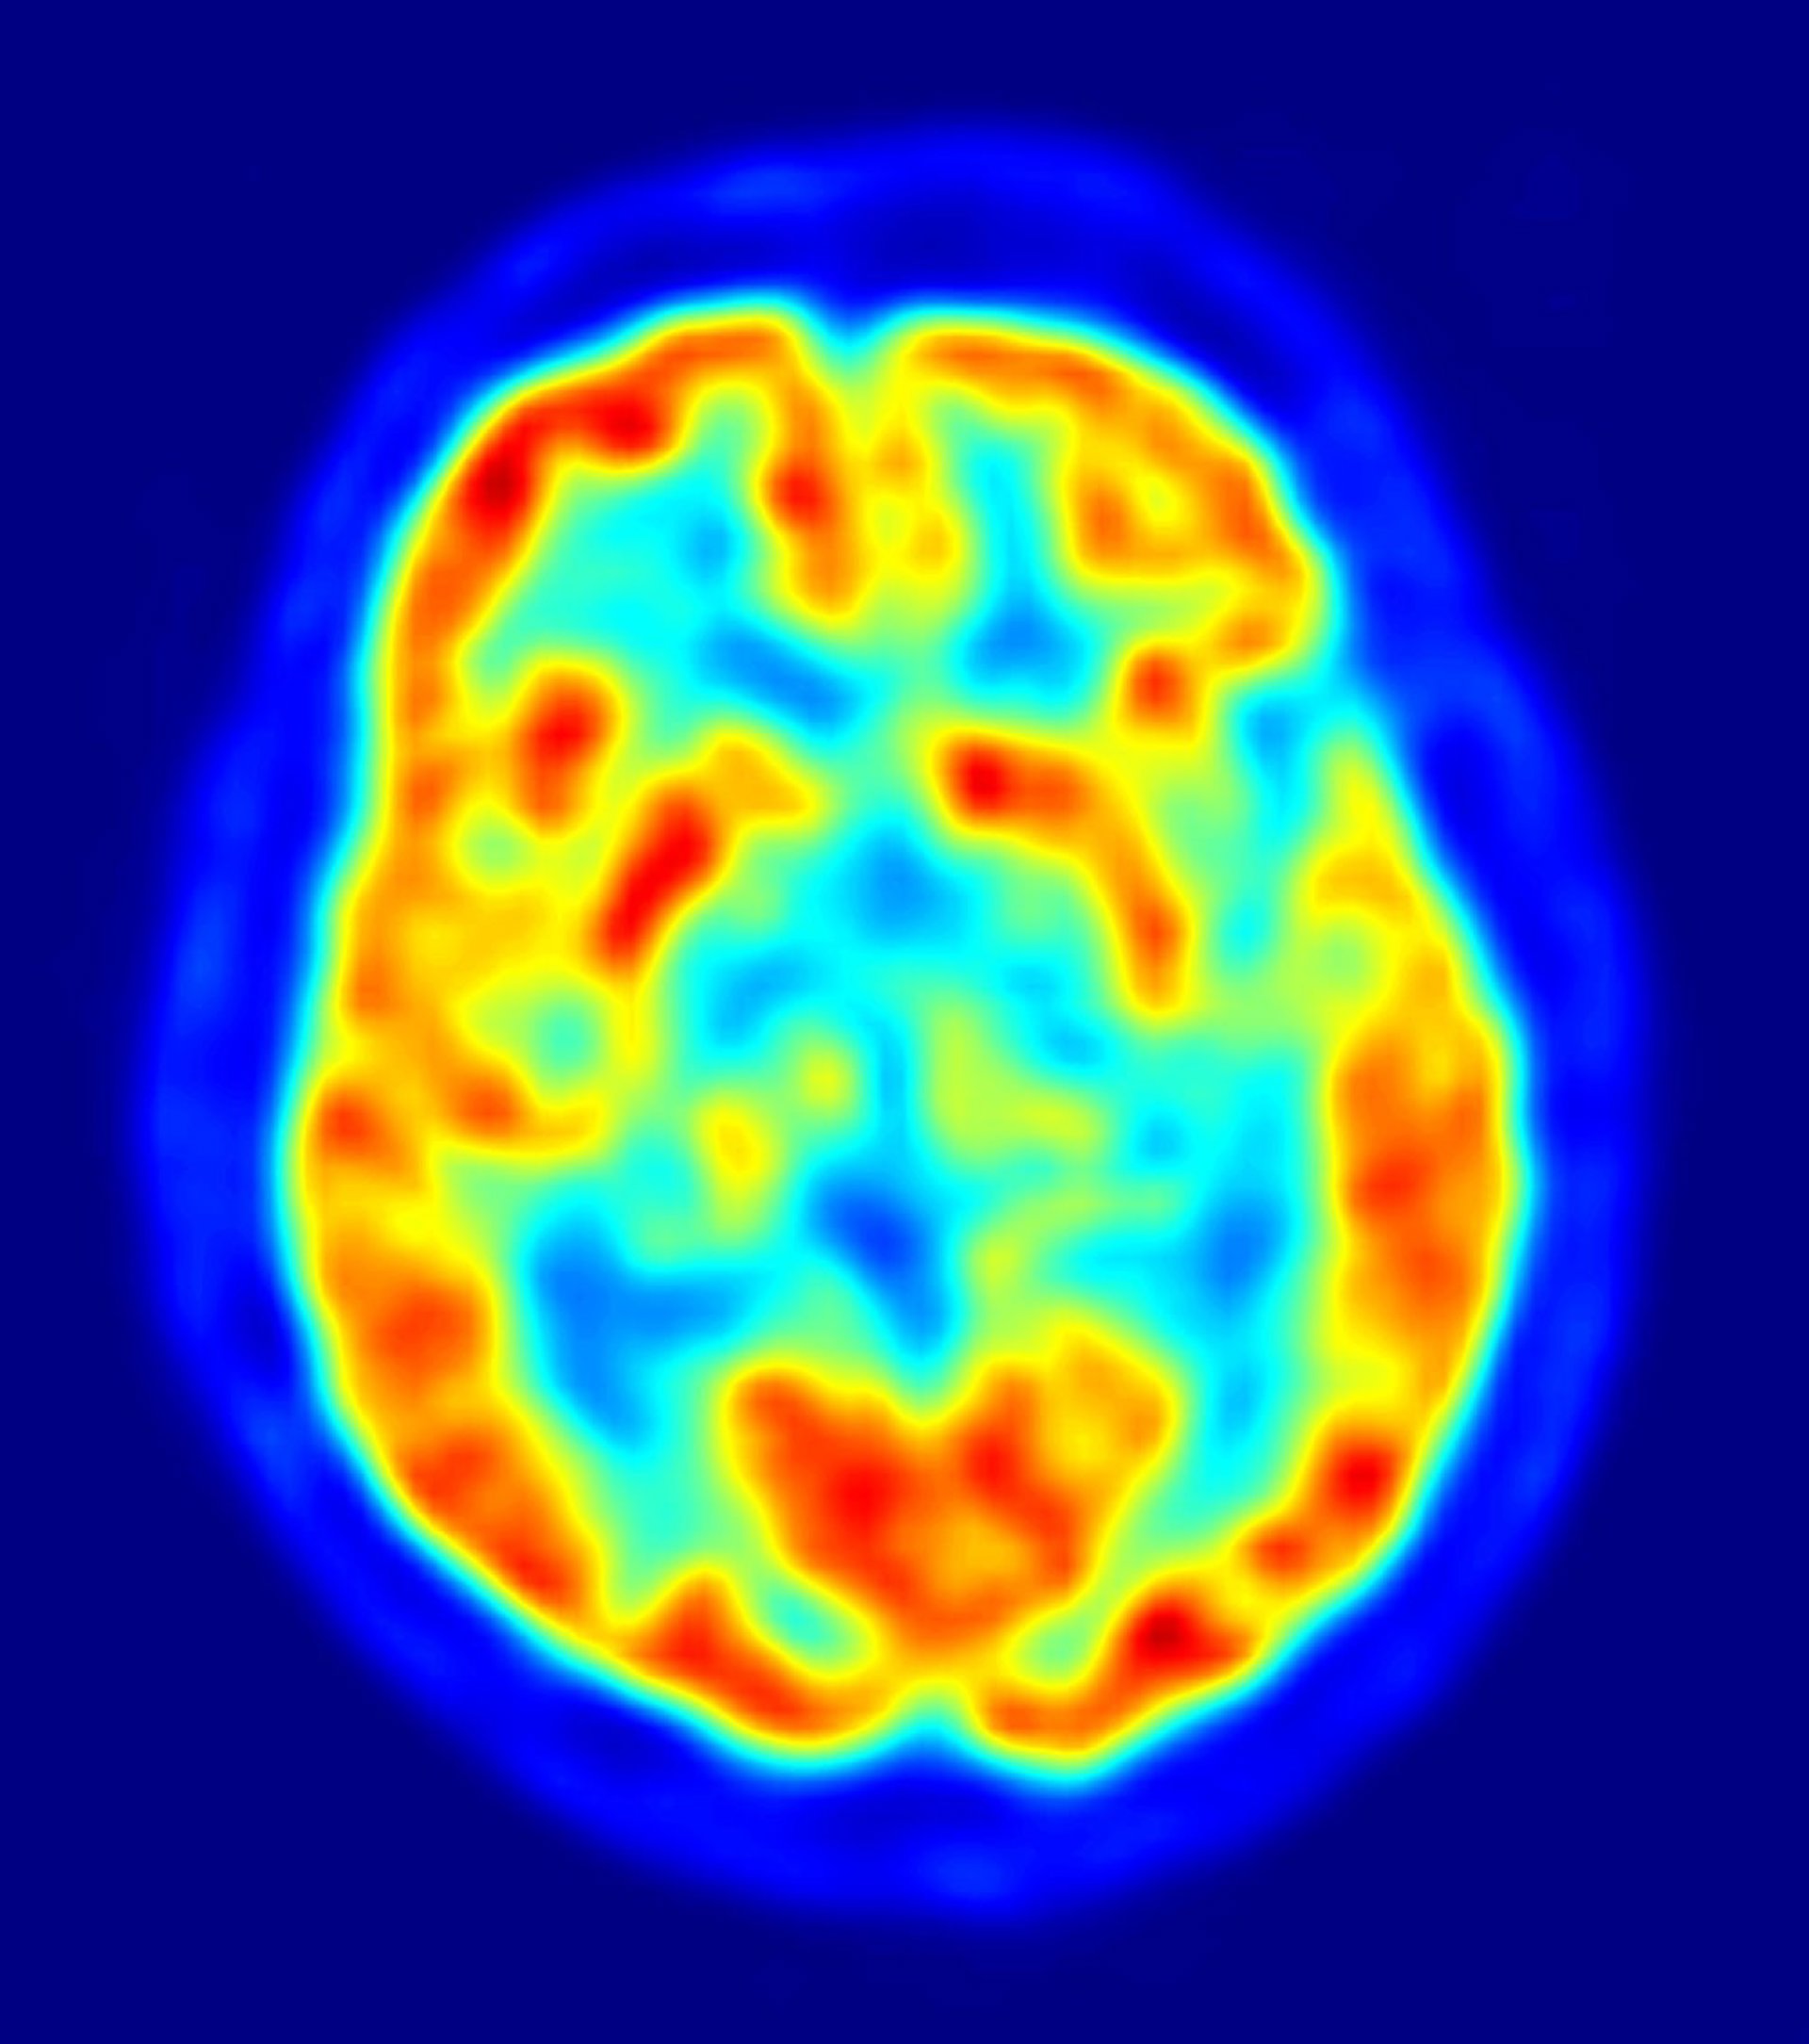

Una de las características de la enfermedad de Alzheimer es la acumulación en el cerebro de la proteína betaamiloide. De hecho, con el tiempo estas proteínas se acumulan con tal densidad que se pueden observar en forma de placas en las exploraciones del cerebro. Comprender el papel que juega el sistema glymphatic en la incapacidad del cerebro para descomponer y eliminar la betaamiloide podría señalar el camino a nuevos tratamientos. En concreto, unos "actores" clave en el sistema glymphatic, como los astrocitos, se pueden manipular hasta la eliminación de los residuos.